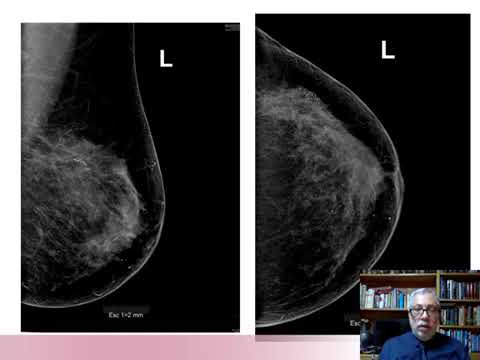

Mamografía Contrastada-Conceptos,Técnicas, Indicaciones y limitaciones

Dr. Marcio Mitsugui Saito

Cancer de Mama – Estado Actual en Latinoamerica y el Caribe

Dra. Ruby Espejo Fonseca

Breast Academy 2021

Dra. Flavia Sarquis

Inteligencia artificial en mamografía “Un futuro promisorio”

Marcelo Gubert